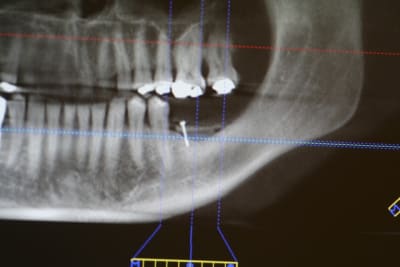

image 10: radio post op

image 11: tomo à 4 mois